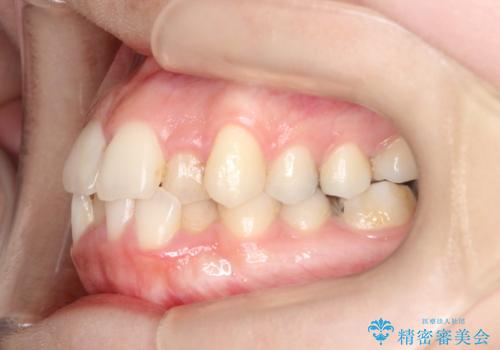

【ワイヤー矯正】前歯の凸凹を非抜歯で治療

- 前歯の凸凹を主訴に来院されました。

側方拡大にてスペースを作ることにより綺麗に前歯を並べることができました。

前歯の凸凹がある場合は治療計画を立てる上でスペースをどのように作るかが重要になります。

今回の場合は主に側方拡大でスペースの確保を行いました。